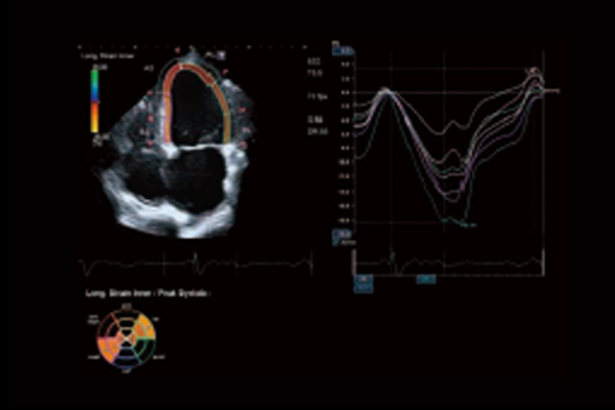

Aplio先進的室壁運動追蹤技術可以即時顯示和定量整體和節段心肌室壁運動變化。